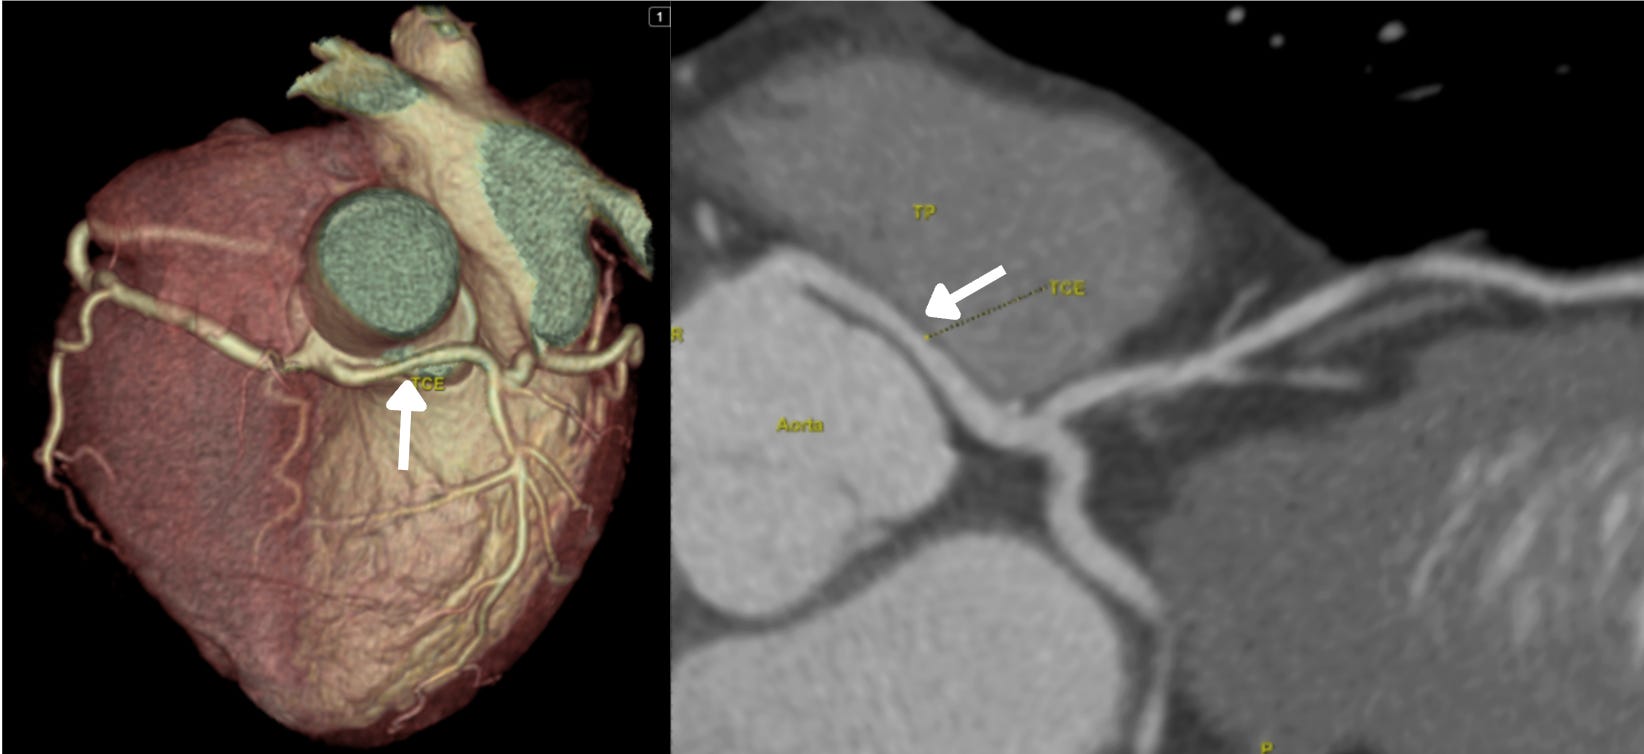

Imagem da semana

Paciente do sexo feminino, jovem, com quadro de dor torácica nos últimos 3 meses, em queimação, associada a estresse emocional e, ocasionalmente, ao esforço físico. Submetida à angioTC acima que observou alteração no TCE (seta branca). Qual o próximo passo?